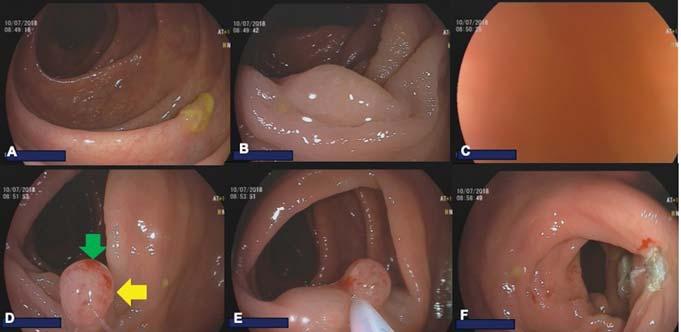

55 Diagnosis of Achalasia

Ofer Z. Fass, MD

Ronnie Fass, MD, MACG